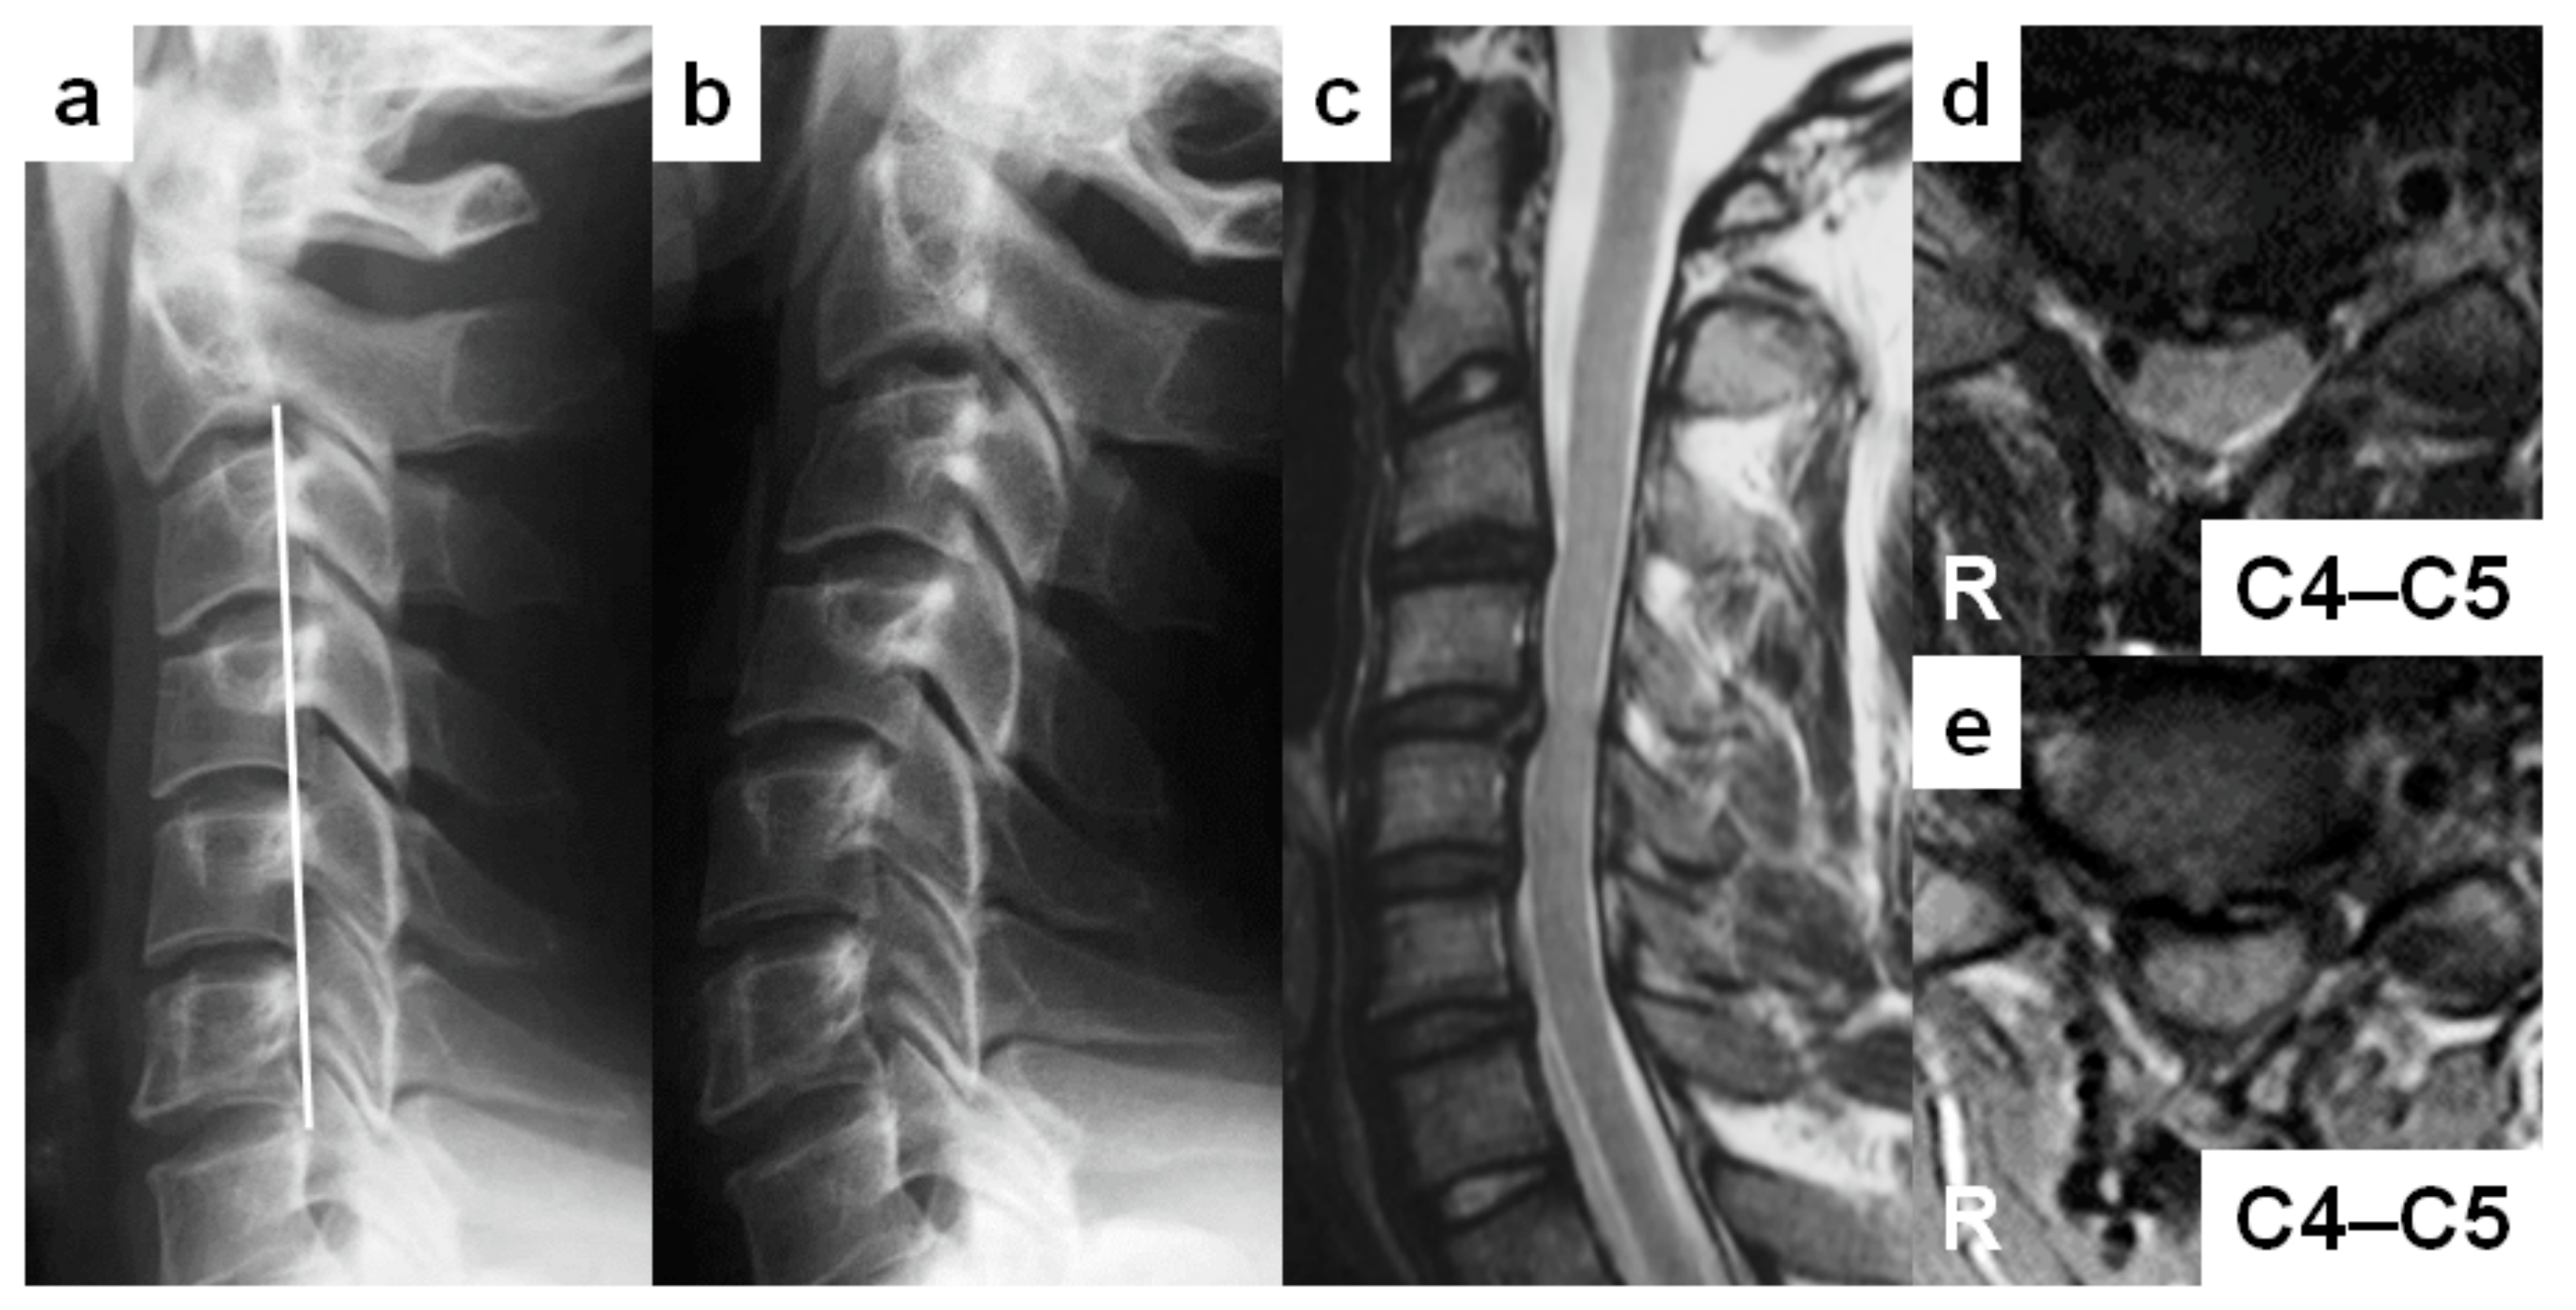

3.4. Case Reports

A 27-year-old man (case no. 1) was referred to our outpatient clinic with complaints of numbness in both ring and little fingers lasting several months. He was a postman and played Judo. He had modest muscle weakness on the left fingers. The Romberg sign was positive. The JOA score at the initial visit was 14 of 17 points. On lateral cervical spine radiographs, the cervical sagittal alignment was “straight” (Figure 2a). The Torg–Pavlov ratio was below 0.80 from C3 to C7. The DVF was positive from C4 to C7. The DNF was also positive at C5–C6, although no obvious vertebral slip was found in full-extension position (Figure 2b). On T2-weighted sagittal MRIs, “degenerative” discs existed from C3–C4 to C6–C7 (Figure 2c). Multi-level spinal cord compression was detected at C4–C5 to C6–C7. An intramedullary increased signal intensity lesion was confirmed at C5–C6, corresponding with the neurologically responsible segment (Figure 2c,d). On T1-weighted axial MRIs, the “angular-edged” spinal cord deformity was observed at C5–C6 (Figure 2e). He took surgery of open-door laminoplasty. His neurological symptoms disappeared with a fully marked JOA score (17 of 17 points) two years after surgery.

Figure 2. Report of a 27-year-old man with cervical spondylotic myelopathy (case no. 1). (a,b) Lateral cervical spine radiographs in neutral (a) and full-extension (b) positions demonstrating the “straight” cervical sagittal alignment. (c) A sagittal T2-weighted magnetic resonance image (MRI) demonstrating “degenerative” discs from C3–C4 to C6–C7, spinal cord compression from C4–C5 to C6–C7, and an intramedullary increased signal intensity lesion at C5–C6. (d) An axial T2-weighted MRI demonstrating the narrowed cervical spinal canal with an intramedullary increased signal intensity area at C5–C6. (e) An axial T1-weighted MRI demonstrating the “angular-edged” spinal cord deformity at C5–C6.